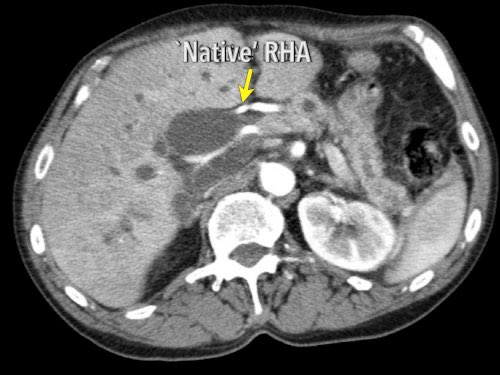

Các động mạch gan có nguyên ủy bất thường có thể là dạng phụ thêm (accessory) hoặc dạng thay thế (replaced).

Động mạch gan phải phụ thêm là một động mạch gan phải bổ sung, trong khi động mạch gan phải thay thế có nguyên ủy bất thường và thay thế hoàn toàn cho động mạch gan phải chính thức (hình minh họa).

Ở những bệnh nhân dự kiến phẫu thuật tụy, điều quan trọng là cần đặc biệt chú ý tìm kiếm nguyên ủy bất thường của động mạch gan phải hoặc động mạch gan chung.

Các động mạch này xuất phát từ phía phải của động mạch mạc treo tràng trên (SMA) và đi qua vùng lân cận đầu tụy, làm tăng nguy cơ xâm lấn của khối u hoặc tổn thương do phẫu thuật.

Tần suất được ghi nhận của các bất thường đặc hiệu này lần lượt là 11-21% và 0,5-5%.

Sự liên quan mạch máu được đánh giá rõ hơn trên ảnh tái tạo mặt phẳng đứng dọc. Có sự áp sát 90 – 180° của động mạch gan phải thay thế (mũi tên trắng) bởi ung thư biểu mô tuyến đầu tụy (đầu mũi tên trắng).

Động mạch gan trái nguyên bản đi theo hướng ra trước hơn, tĩnh mạch cửa nằm ở giữa.

Cuộc phẫu thuật là cắt bỏ diện R1.

Các hình ảnh axial của cùng bệnh nhân có chú thích.